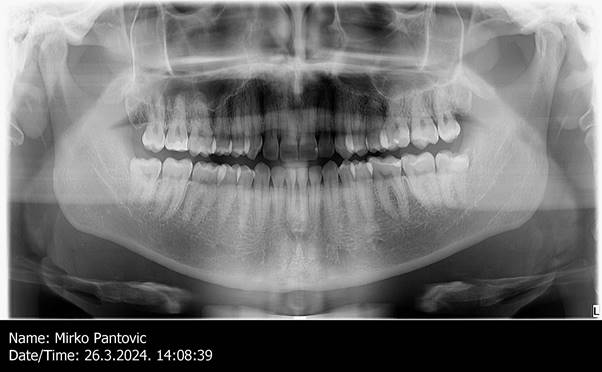

digital panoramic 2D orthopantomograms of all teeth, joints, and sinuses